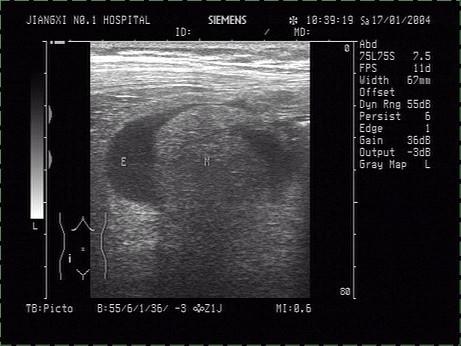

问题 患者,右下腹压痛,体温38.5℃。根据右下腹声像图表现,诊断是?(?)

选项 A.腹膜炎 B.结肠癌 C.阑尾脓肿 D.单纯性阑尾炎 E.腹水

答案 C